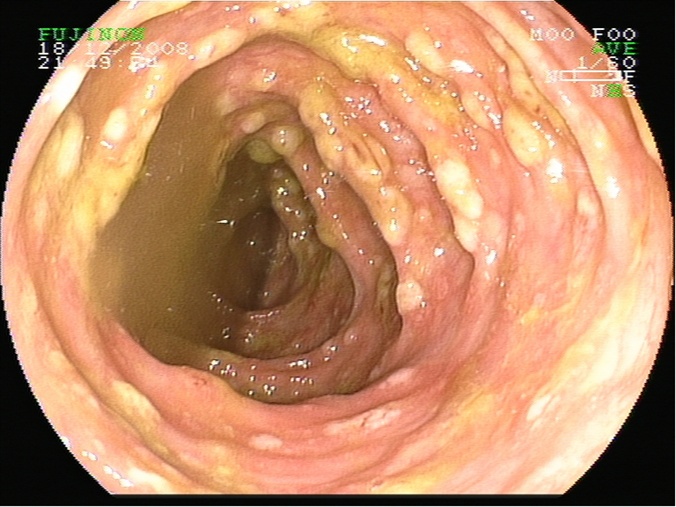

Colitis pseudomembranosa